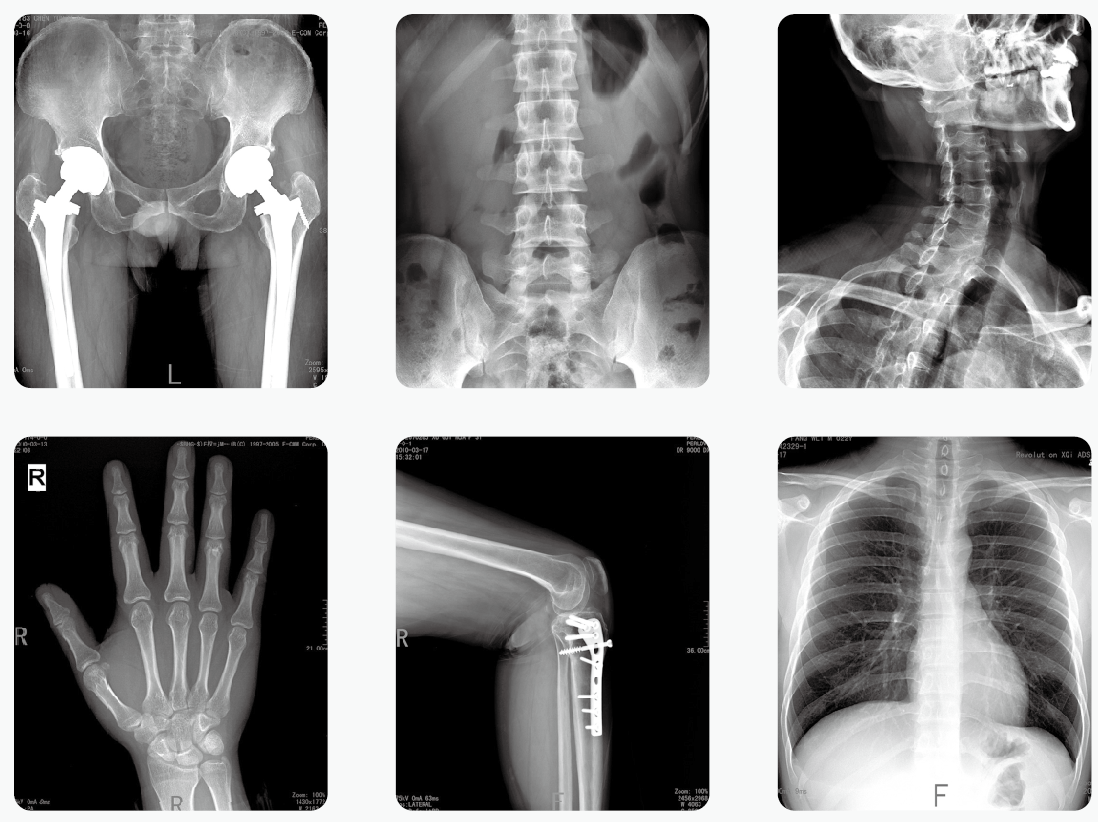

2019-nCoV肺炎的診斷都需要做X光檢查來確定。2月2日,中華醫(yī)學(xué)會影像技術(shù)分會傳染病影像技術(shù)專業(yè)委員會專家共識協(xié)作組發(fā)布了《新型冠狀病毒(2019-nCoV)感染肺炎放射檢查方案與感染防控專家共識》。其中明確提出移動數(shù)字化X光機(jī)在診療過程中的重要性,將其作為肺炎篩查和診斷的重要工具。

移動數(shù)字化X光機(jī)、CT是新型冠狀病毒感染的肺炎檢查的可靠依據(jù)。如果得了新型冠狀病毒肺炎,早期X線胸片影像學(xué)表現(xiàn)主要是雙肺出現(xiàn)斑片影,以及間質(zhì)性的改變。新型冠狀病毒肺炎影像學(xué)表現(xiàn)多樣且與其他類型肺炎存在相似影像學(xué)表現(xiàn),鑒別困難。尤其和其它病毒性肺炎鑒別時,需結(jié)合流行病學(xué)、實(shí)驗(yàn)室檢測相關(guān)資料,如核酸檢測。

普愛醫(yī)療器械廠家的移動數(shù)字化X光機(jī)專門用于檢查疑似新型肺炎患者,按照要求達(dá)到有效隔離和有效防護(hù),在這次新型冠狀病毒感染的防控中可以發(fā)揮重要作用。